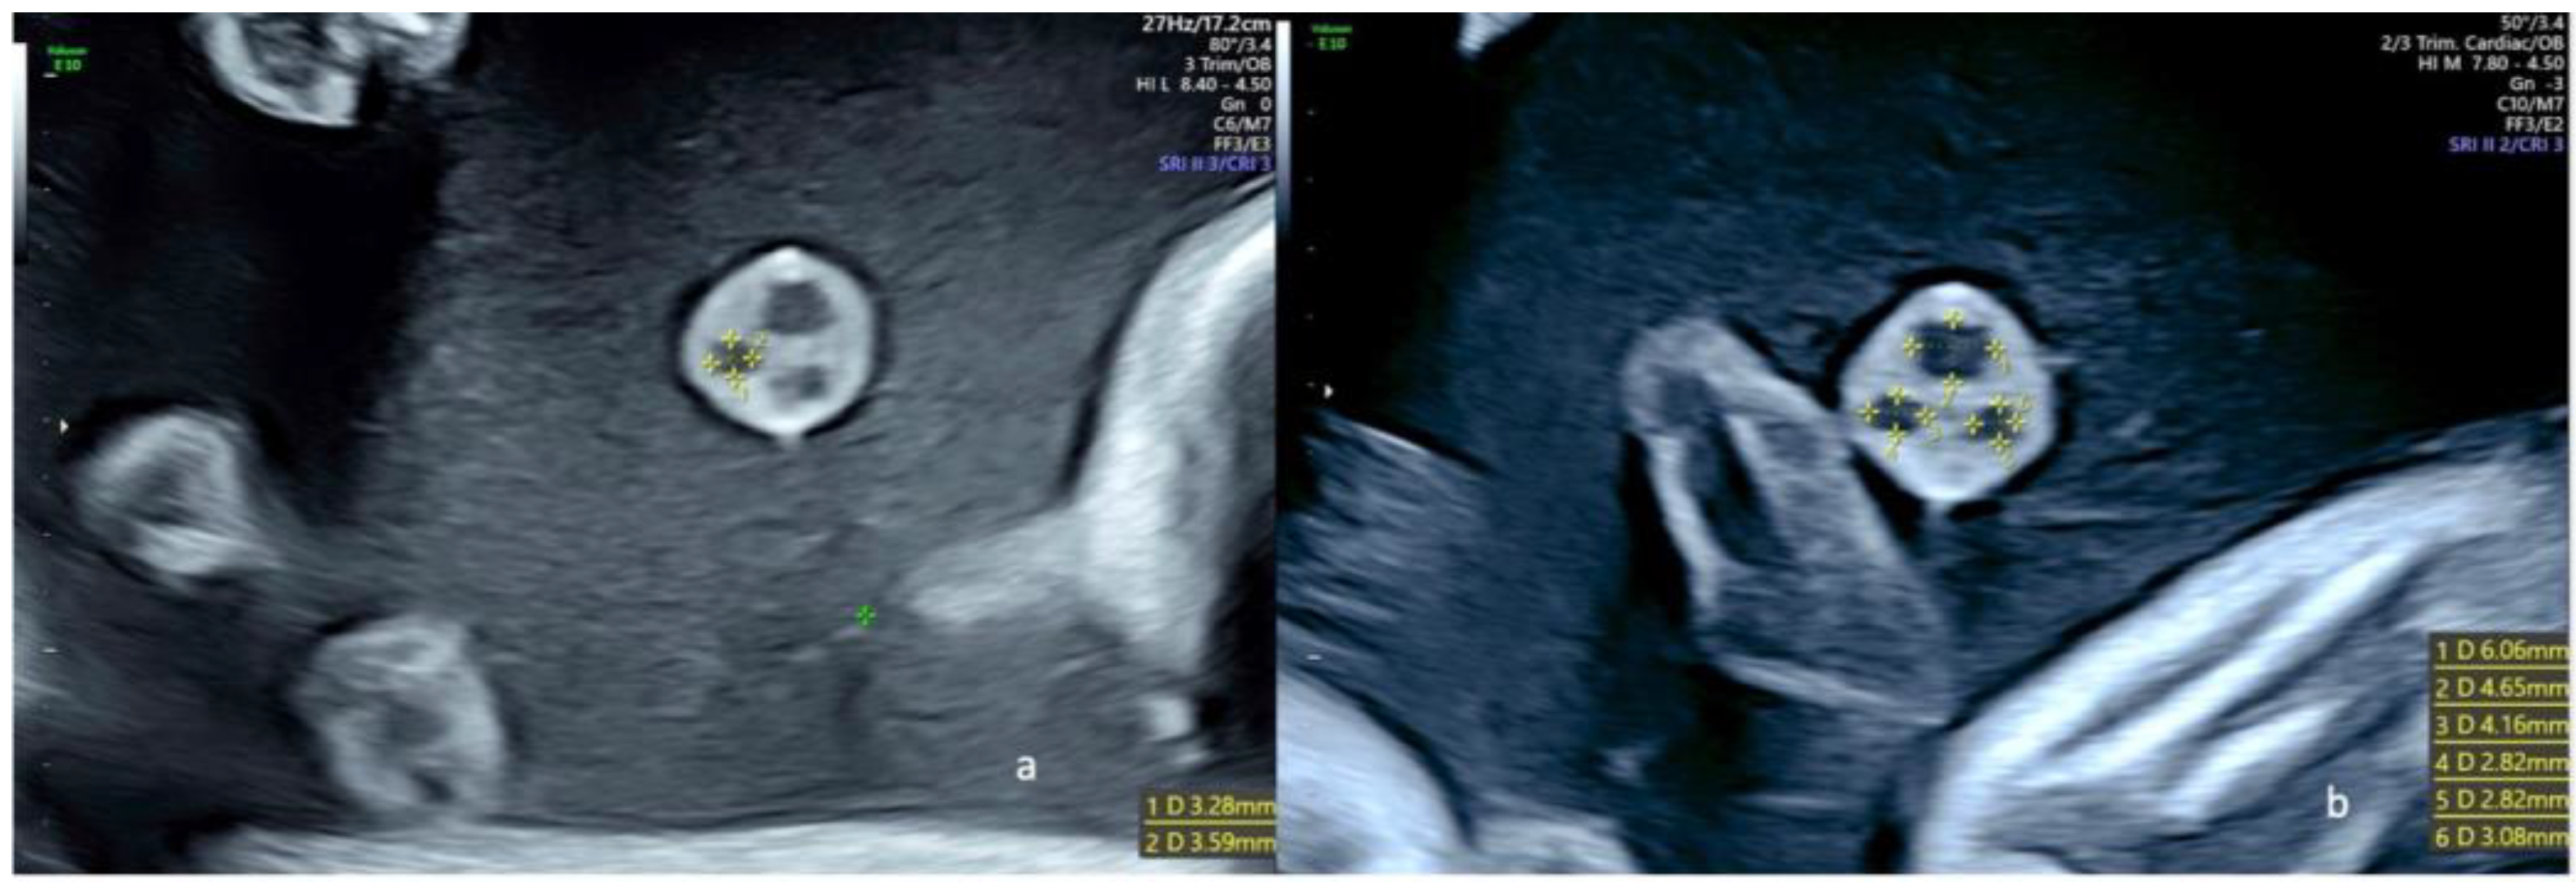

Figure 3.

Ultrasound views of a free umbilical cord in fetuses with a regular umbilical cord at 22 weeks of gestation; (a) one of the two umbilical arteries was measured in a transverse view of a free loop, and the diameters were 3.28 × 3.59 mm; (b) transverse view of a free loop showing the measure of both umbilical arteries (4.16 × 2.82 and 2.82 × 3.08 mm) and the umbilical vein (6.06 × 4.65 mm).